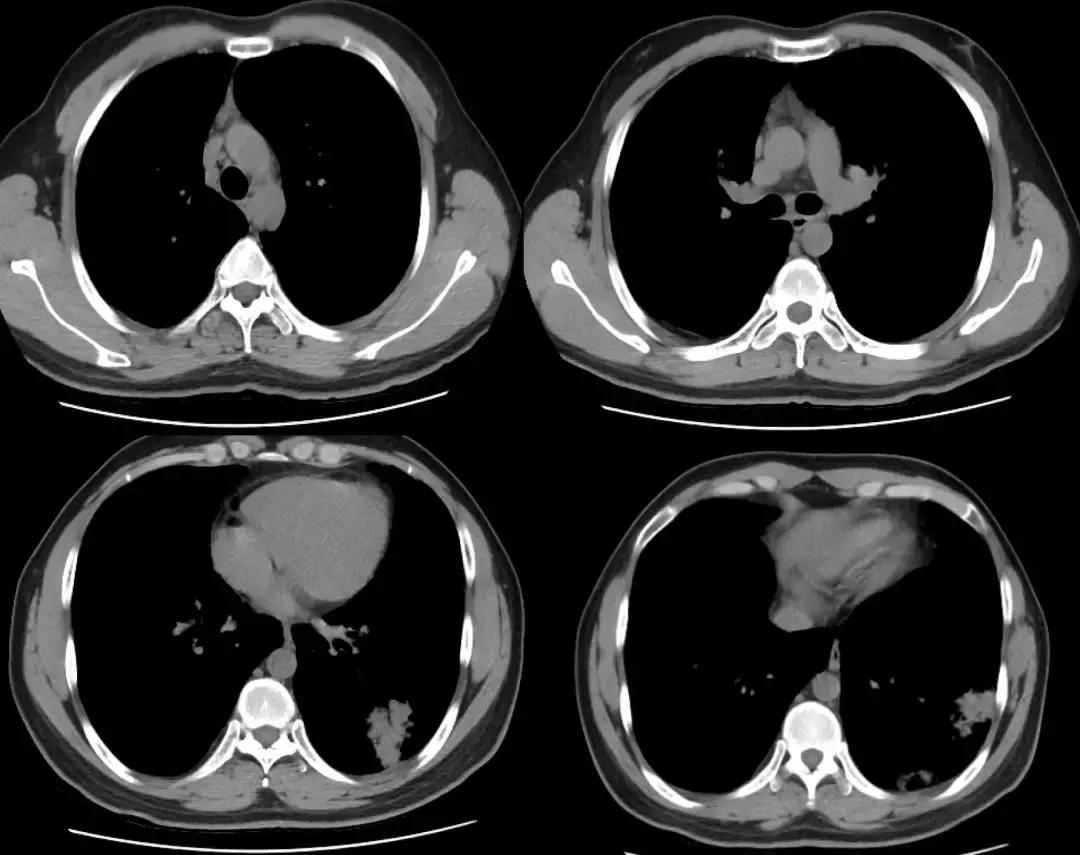

胸部CT(2017-7-31 我院门诊):两肺野弥漫磨玻璃影,性质待定;两肺上叶陈旧性病变。(如下图)

胸部CT(2018-1-18 我院门诊):两肺野弥漫磨玻璃影,较前变化不明显;新增左肺下叶基底段片状密度增高影,建议治疗后复查;两肺上叶陈旧性病变:

复查胸部CT(2018-1-29),对比原片如下图:

1、两肺野弥漫病变较前未见明显变化,两肺上叶陈旧病变同前

2、左肺下叶片状密度增高影较前范围增大,密度增高

3、纵膈内多发淋巴结,大者位于气管隆突下,短径约1.1cm,较前未见明显变化;余基本同前。